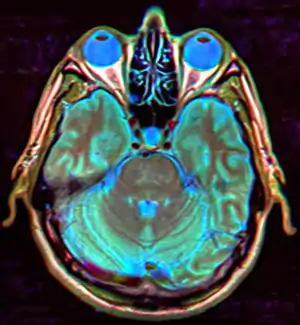

| Diagnostic method | MRI, CT scan[1] |

The major differential to consider in empty sella syndrome is intracranial hypertension, of both unknown and secondary causes, and an epidermoid cyst, which can mimic cerebrospinal fluid due to its low density on CT scans, although MRI can usually distinguish the latter diagnosis.[10]